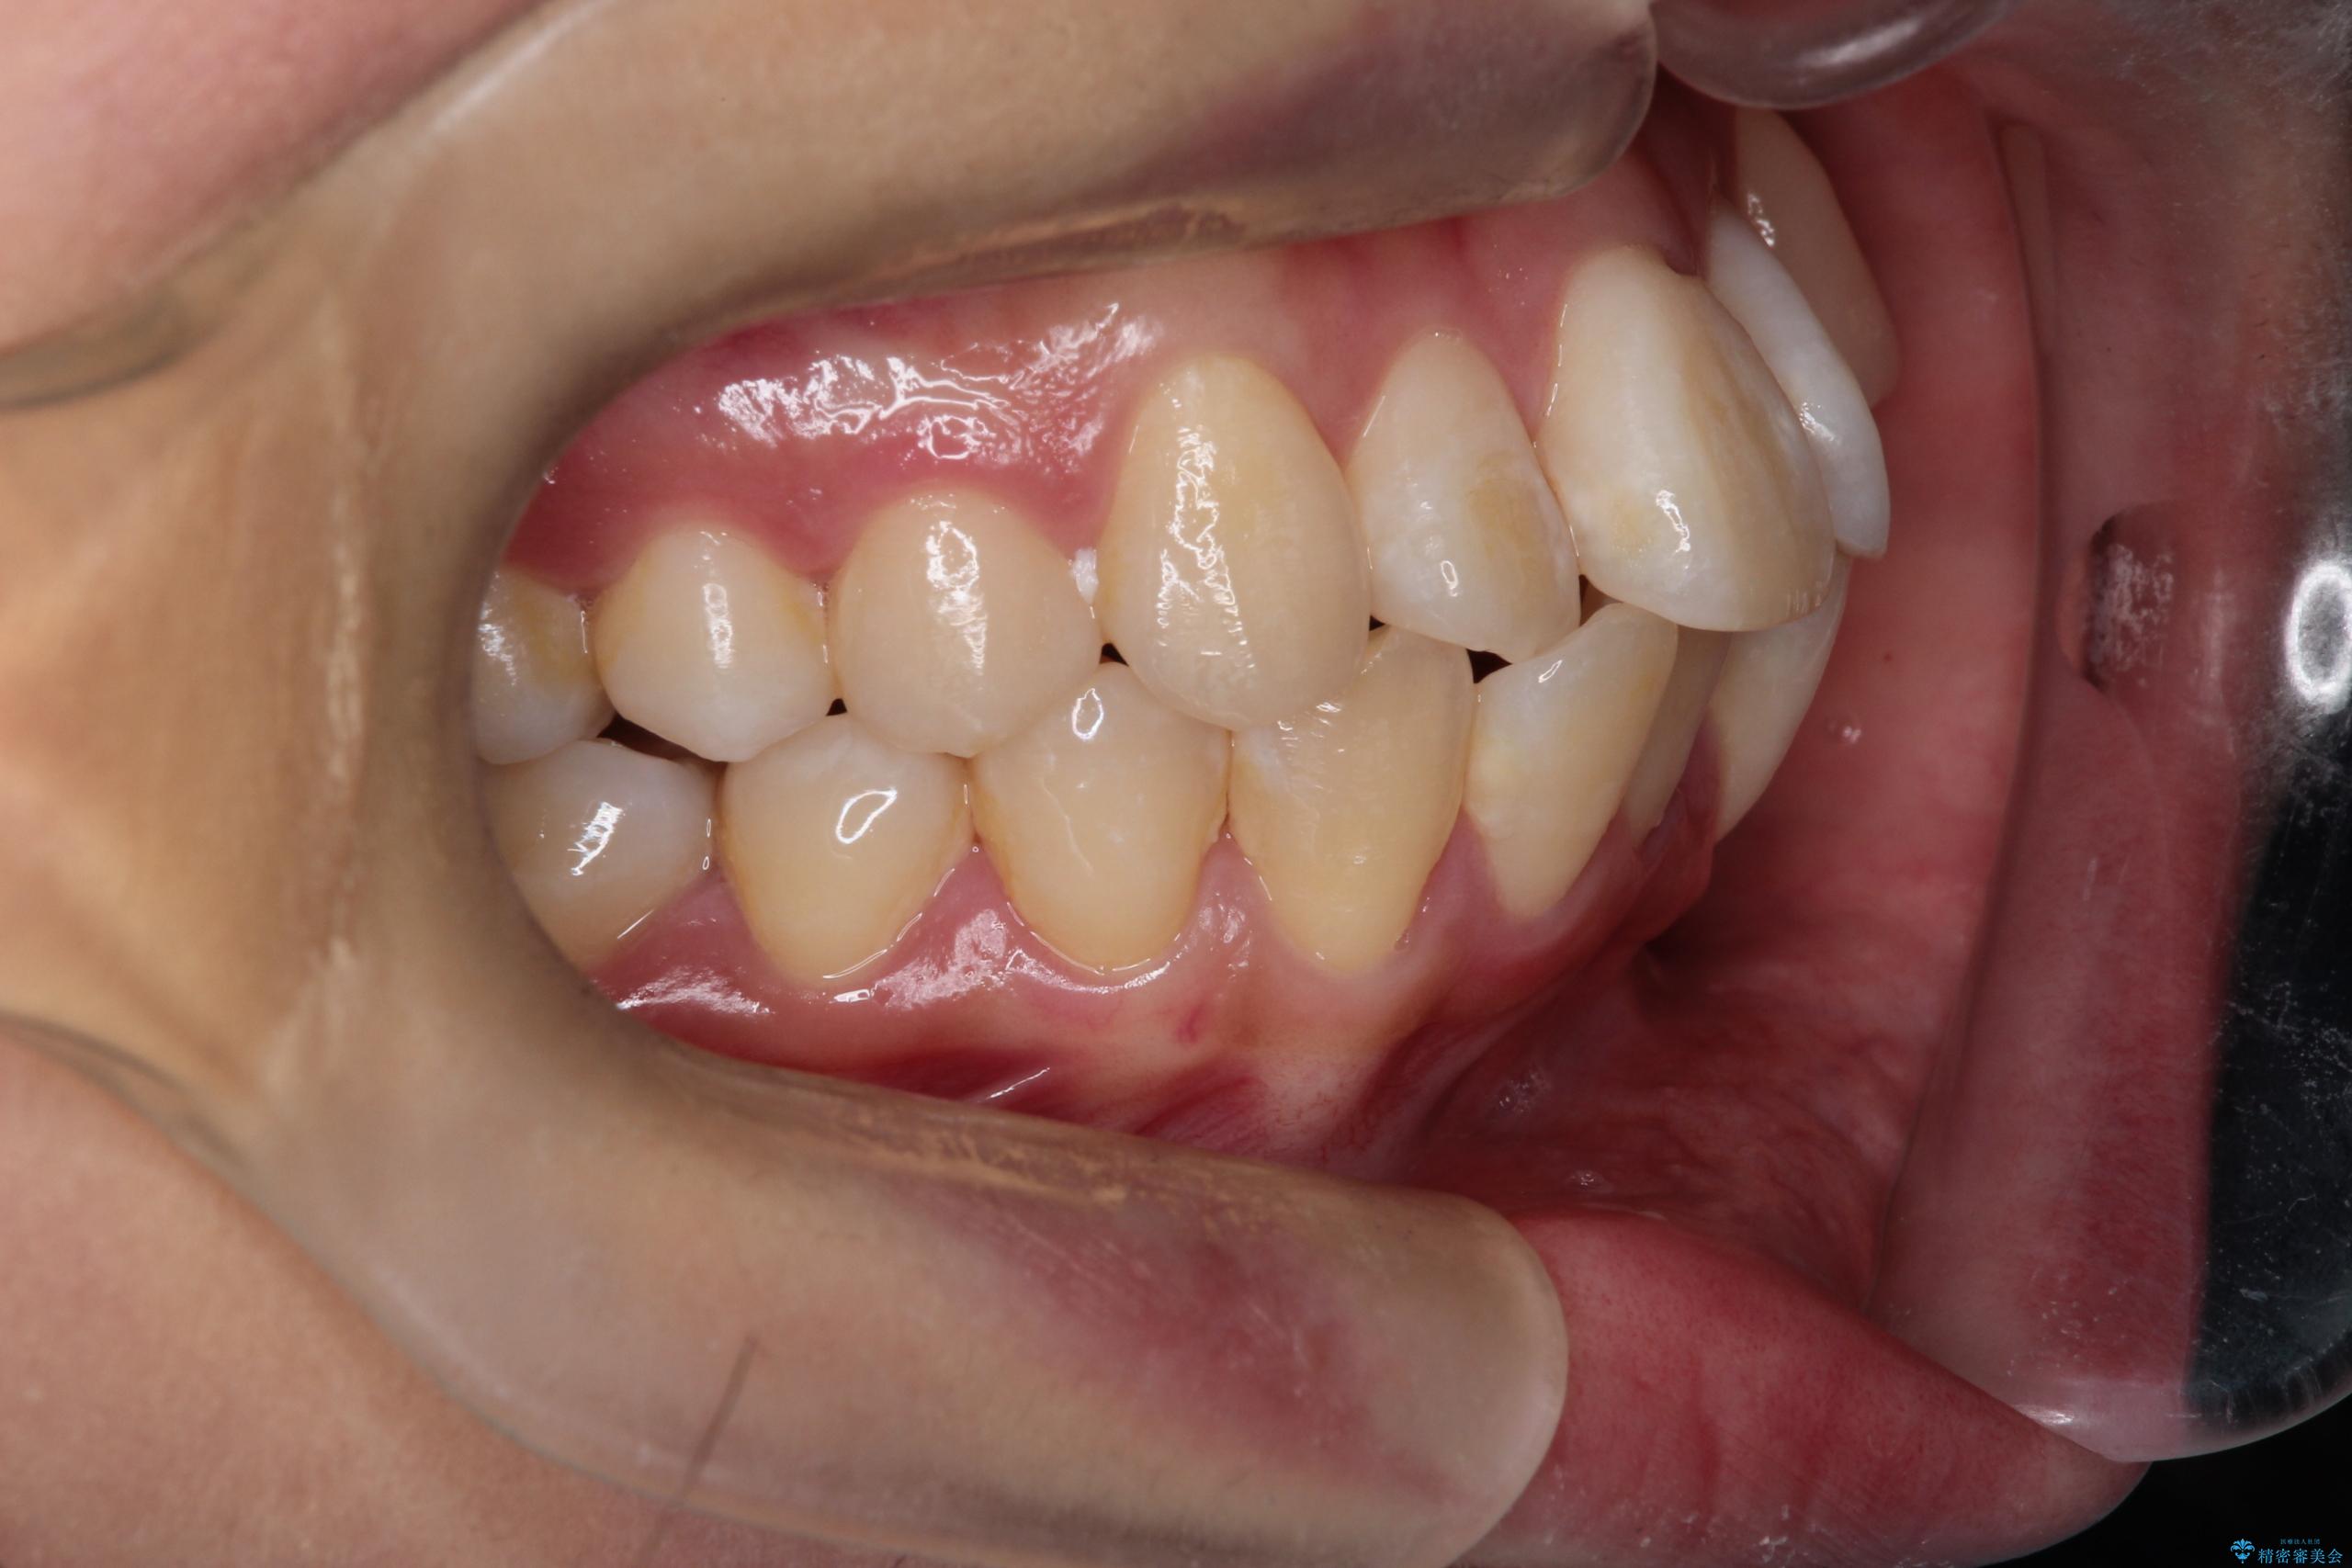

- 八重歯(叢生)と、上下の歯の中心線(正中)がずれていることを主訴にご来院されました。精密な検査の結果、歯列全体のスペースが大幅に不足しており、八重歯を正しい位置に配列し、正中のズレを改善するためには、上下左右の第一小臼歯を抜歯する必要があると診断。装置には、目立ちにくい審美ワイヤーを使用し、見た目を気にせず、機能性と審美性が完璧に整った咬み合わせを目指す治療計画を立案しました。

今回の矯正治療では、まず計画通り上下左右の小臼歯4本を抜歯し、八重歯や正中のズレを解消するための十分なスペースを確保しました。装置には、目立ちにくい白いブラケットとワイヤーを使用した審美ワイヤー矯正を採用。

八重歯: 突出していた八重歯を歯列内に誘導し、デコボコを解消しました。